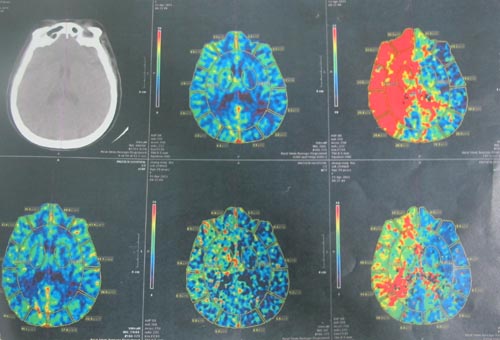

颈动脉CTA:左侧颈内、颈外动脉轻度狭窄,右侧颈外动脉、左锁骨下动脉起始段中度狭窄,右侧颈内、右锁骨下动脉起始段重度狭窄,右侧椎动脉重度狭窄。

该患者为老年女性,双侧颈动脉狭窄,且右侧为重度,患者反复间断头晕,肢体乏力1年余,有脑梗塞病史10年,高血压病5年,高脂血症3年,疑似冠心病,为脑卒中高危人群,且狭窄程度符合CEA手术标准,故予以手术治疗。2011年4月27日,协作组张勤奕教授顺利为其实施了右侧颈内动脉CEA。